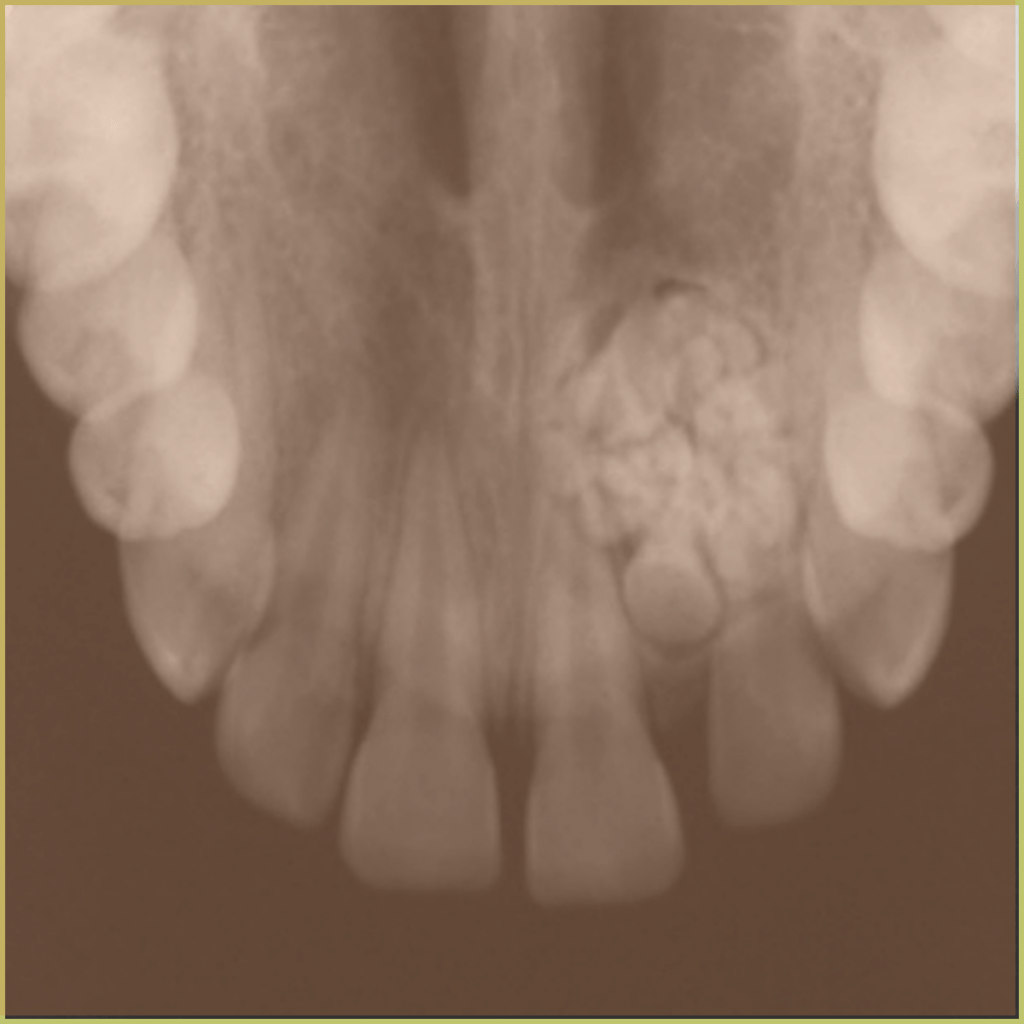

ODONTOMAS

Odontomas are the most common hamartomatous benign mixed odontogenic tumors of the jaw, composed of all the building blocks of teeth (enamel, dentin, cementum, and pulp tissue). They develop from stimulation of the epithelial dental lamina. Variants include compound odontomas (small tooth-like structures), complex odontomas (aggregation of dentin, enamel and cementum) and cystic odontomas. The common clinical presentation includes:

- Well-defined mixed radiolucent and radiopaque lesions.

- Visible within the alveolar segment of the maxilla and mandible.

- Complex form is the most common in the mandible, compound form is the most common in the anterior maxilla.

- May contain a few small “teeth” or large numbers of tiny tooth-like structures.

- Asymptomatic and usually discovered incidentally.

- Can cause alveolar expansion, jaw expansion, and interfere with tooth eruption.

Diagnosis is based on the lesion history, clinical presentation and microscopic findings, which usually includes evidence of dental hard tissues. Your differential diagnosis should include: